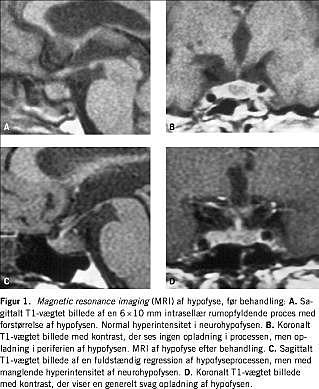

I. En 55-årig kvinde havde i to måneder haft almensymptomer, sinuitis, rinitis med skorpedannelse, epistaxis, hæmoptyse, episkleritis og polyuri (7,2 l pr. døgn). Ved en næseslimhindebiopsi sås der kronisk inflammation og Pr3-antineutrofile cytoplasmatiske antistoffer (ANCA) var positiv (>100 enheder pr. ml). En tørsteprøve viste partiel CDI. Adenohypofysefunktionen var normal. Ved en magnetic resonance imaging (MRI) (Figur 1) sås der diffust forstørret hypofyse med en kontrastfattig intrasellær rumopfyldende proces. Neurohypofysen viste normal hyperintensitet på T1-vægtede billeder. En somatostatinreceptorskintigrafi (SRS) viste øget aktivitet svarende til cavum nasi, men et upåfaldende hypofyseleje. Patienten responderede på behandling med højdosis prednisolon, methotrexat og desmopressin. MRI af hypofysen efter to år viste komplet regression af hypofyselæsionen, men en manglende hyperintensitet af neurohypofysen. Den medikamentelle behandling forblev uændret.

I litteraturen beskrives to hyppige MRI-fund, som også fandtes hos vores patienter: 1) manglende hypertintensitet af neurohypofysen på T1-vægtede billeder, hvilket er foreneligt med CDI uanset ætiologi [2], og 2) intrasellær rumopfyldende proces uden kontrastopladning. Desuden er der beskrevet kontrastrige læsioner af infundibulum og hypothalamus. I seks ud af 12 beskrevne tilfælde opnåedes komplet eller delvis regression af CDI efter behandling for WG, hvorimod vores patienter havde uændret CDI trods delvis svind af de rumopfyldende processer og adækvat behandling af WG.